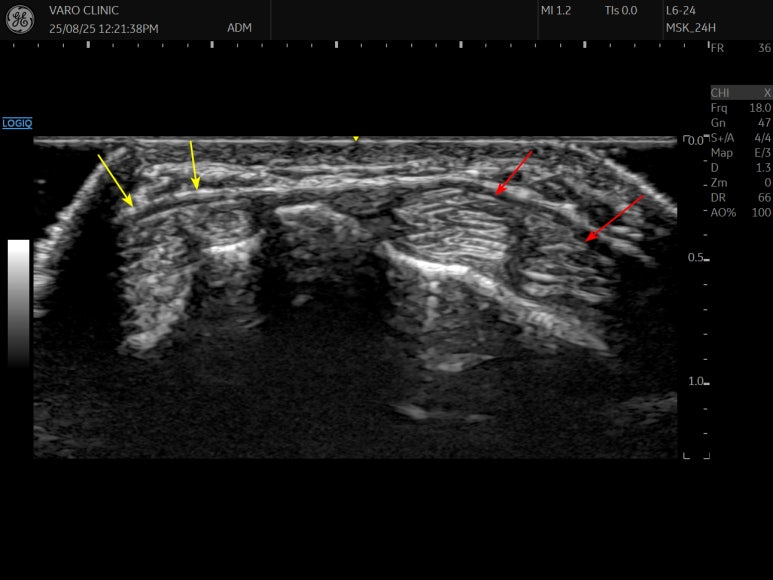

좌측의 노란색 화살표는 No.1 첫번째 구획우측의 붉은색 화살표는 No.2 두번째 구획입니다.**

바로 근접해 위치해있죠?

실제 주행하는 모습을 보겠습니다.

첫번째 구획이

두번째 구획 위를

훅 미끄러지듯 지나가는 것이 보이시나요?